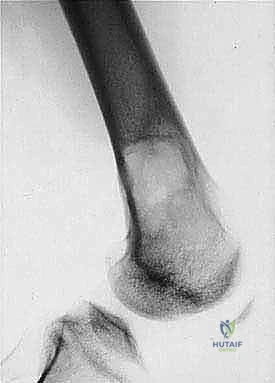

* الساركوما العظمية (Osteosarcoma): الأكثر شيوعاً، تظهر عادة حول الركبة (أسفل الفخذ أو أعلى القصبة).

2. كتلة أو تورم: ظهور ورم محسوس يزداد في الحجم تدريجياً، سواء كان مؤلماً أو غير مؤلم.

3. الكسور المرضية: حدوث كسر في العظم نتيجة إصابة طفيفة جداً لا تسبب كسراً في العظم السليم.

| حدود الورم في الأشعة | واضحة، محددة بدقة (Sclerotic margin) | غير واضحة، متآكلة (Moth-eaten appearance) |

| اختراق قشرة العظم | نادر جداً | شائع جداً، يمتد للأنسجة الرخوة المحيطة |

المرحلة الأولى: استئصال الورم (Resection)

يتم فتح الجلد والأنسجة بعناية فائقة. التحدي الأكبر هنا هو فصل الورم عن الأوعية الدموية والأعصاب الرئيسية المغذية للطرف. يستخدم الدكتور هطيف تقنيات الجراحة الميكروسكوبية لضمان سلامة هذه الهياكل الحيوية، مما يحافظ على حيوية الطرف وحركته.